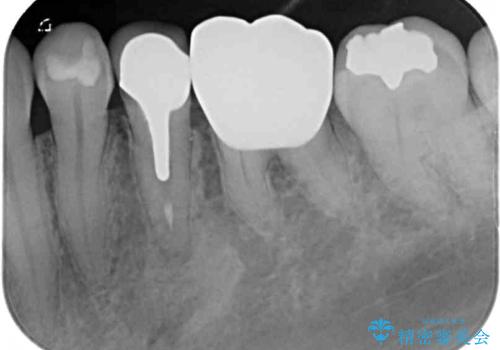

- 奥歯の銀歯をセラミックの白い歯にして、しみる症状も改善したいとのことで来院された患者様です。

知覚過敏の症状が強い歯と、銀歯の範囲や銀歯の下のむし歯が大きい歯は、インレー修復では対応が難しいためオールセラミッククラウンで、インレー修復で対応が可能な歯ではセラミックインレーにて修復することとしました。